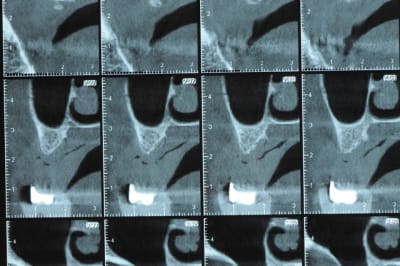

un cas pour PXAV.

ça c'est le domaine de pxav.

qu'en penses tu ?

j'ai besoin de 4 implants au maxillaire pour faire tenir son complet.

dans la zone postérieur, pas de problème, mais devant, c'est une autre histoire.

Non sans décorner, superbe cas de début pour expansion, bone splitting et tout et tout.

la corticale a l'air tiptop, par contre en cas d'expansion il faut eventuellemnt augmenter le nombre d'implant à 6 pour compenser eventuellement le manque d'epaisseur 'avis personnel)

Je suis sceptique sur la gestion de ce cas par bone splitting puisqu'il met parait très difficile d'obtenir un volume osseux peri-implantaire crestal suffisant et satisfaisant.

+1 Olive, ce serait à mon avis plus prédictible avec des greffes. Je doute qu'on puisse obtenir suffisamment d'os en vestibulaire et en palatin des implants en splittant une crête aussi fine.

De ce que j’ai vu du cas de D57 c’est me semble t il un magnifique cas d’expansion, ce qui ne veut pas dire rien d’autre

Une petite étude de ton cas D57

Sous réserves bien sur de voir l’animal en vrai

Les zones exploitables radiologiquement parlant:

Coupes implant

2,3 40100

4,96 35130 avec sinus lift mais difficile

5,25 35150

6,02 35130

6,78 35115 après réduction de hauteur de crête

7,26 35115 après réduction de hauteur de crête

8,51 35150

10,43 40115 ou 50115

11,10 40115

Ce qui nous fait 9 implants possible évidement avec un comblement de sinus on augmenterait encore les zones implantable mais ce n’est pas le but recherché, avec 8 (4+4) il doit être possible de faire une belle barre support de complet